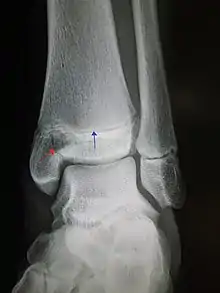

| An X-ray of the left ankle showing a Salter–Harris type III fracture of medial malleolus. Red arrow demonstrates fracture line while the blue arrow marks the growth plate. | |

- Type III – A fracture through growth plate and epiphysis, sparing the metaphysis:[9] 8% incidence